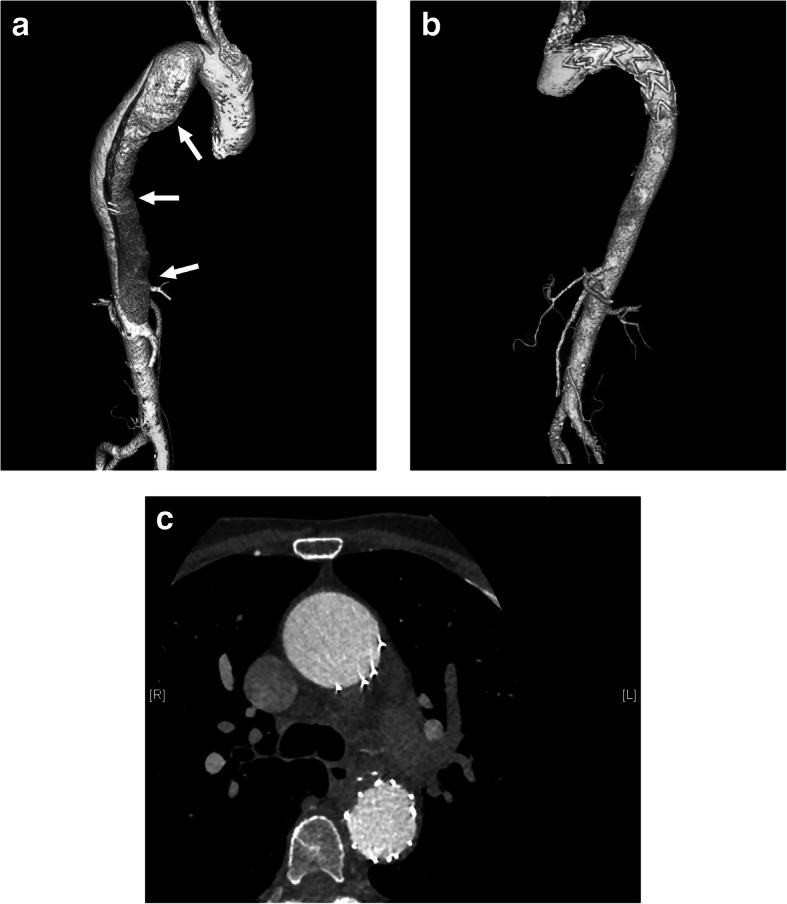

A 56-year-old woman presented to our hospital with a history of a left adrenal mass and high blood pressure. She had been diagnosed with hypertension in 2003. Her blood pressure was controlled with amlodipine and was less than 140/90 mmHg at a dose of 5 mg daily. She reported frequent fatigue. She was admitted to the hospital, diagnosed with hypokalemia and treated with potassium supplements. In 2009, she presented with chest pain and back pain. A computed tomography (CT) angiogram demonstrated dissection of the descending aorta (Fig. 1a). Thoracic endovascular aortic repair (TEVAR) with a stent graft was successful. At the same time, she was found to have a left adrenal mass approximately 1 cm in diameter. She was started on valsartan to reduce blood pressure. Her blood pressure was 130–140/90–100 mmHg initially but gradually became difficult to control. Despite treatment with three antihypertensive drugs, her blood pressure still reached 180/110 mmHg. In 2017, repeat aortic CT revealed no new dissection (Fig. 1b, c). CT of the abdomen showed that the left adrenal mass had grown to more than 3 cm in diameter (Fig. 2).

Fig. 1.

CT angiograms. a Dissection of the descending aorta in 2009 (arrows). b, c Repeat study in 2017 revealed no new dissection after TEVAR. CT: computed tomography; TEVAR: thoracic endovascular aortic repair